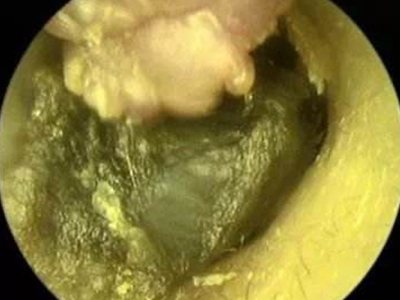

以上为外耳道乳头状瘤外耳道里长了块肉瘤图。

外耳道乳头状瘤患者进行检查时可见外耳道内有肉瘤样的肿块,可表现为表面凹凸不平,质地较硬,会伴有外耳道堵塞感、听力减退的症状。